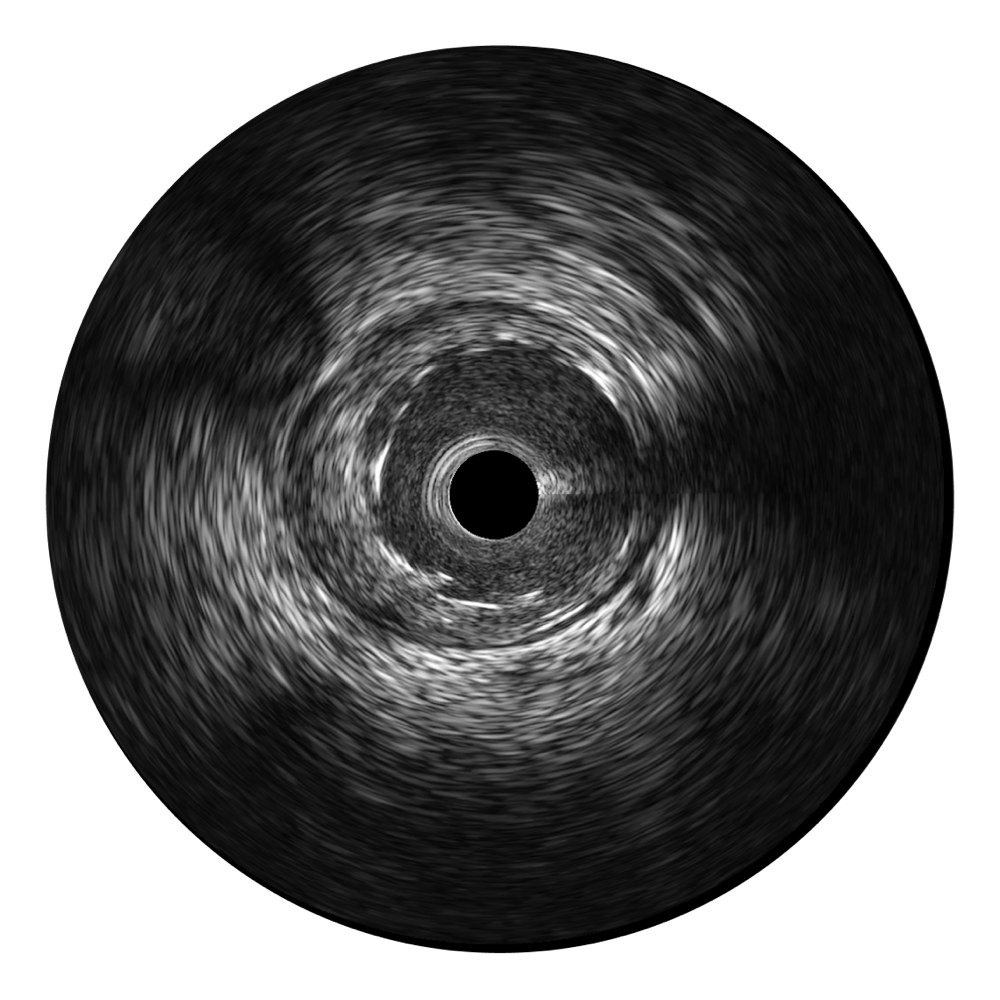

• 玖鼎集团宽频IVUS图像

对比传统IVUS导管成像,玖鼎集团宽频IVUS图像的近场支架梁显影更细腻,远场中膜外血管仍清晰可辨,兼顾远中近,兼顾分辨力与穿透深度